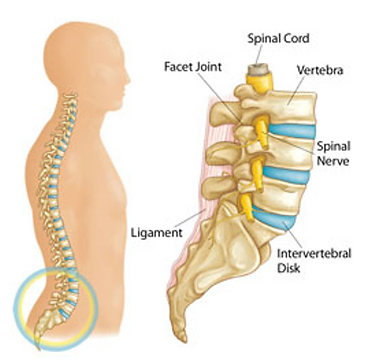

Pain Management 101

3 out of 4 people have experienced chronic/ recurring pain or have a family member who has experienced such pain. Almost 62% of pain sufferers have had their pain for more than a year. A majority of adults (57%) have experience chronic or recurring pain including 54% of patients between 18-34

Chiropractic & Pain Case Studies 1

The 34-year-old male coming from ER with a diagnosis of sciatica. Complaining of severe 8/10 VAS Low back right buttock and leg pain. Started 3 weeks prior after playing softball. He was then also involved in an MVA a week prior to the visit, which worsened symptoms

Chiropractic & Pain Case Studies 2

The patient underwent Left L5-S1 endoscopic discectomy and annuloplasty on 11/29/2016. Upon follow up on 01/06/2017 patient reported 70% relief of his pain

“The best he has felt in 5 years”

Chiropractic & Pain Case Studies 3

Saw Dr. K in Allen for three months to get Airrosti treatments. Pain was reported as Sharp in the low back, constant, occasionally radiating to both legs. Worse with sitting, driving, standing up holding his daughter

Chiropractic & Pain Case Studies 4

Can mobilize a facet joint that has arthritis and an adjacent facet cyst temporarily irritate a nerve root? What if the patient does not get good and/or sustained relief from a combination of epidural steroid injections and facet injections?

Spine and Pain Case Studies 1

Patient back pain for 15 years Significantly worsened and is shooting down the right leg since 2 weeks prior. History of MVA in 1999 and 2004 Pain is constant, burning, sharp, stabbing, and tingling in the right leg